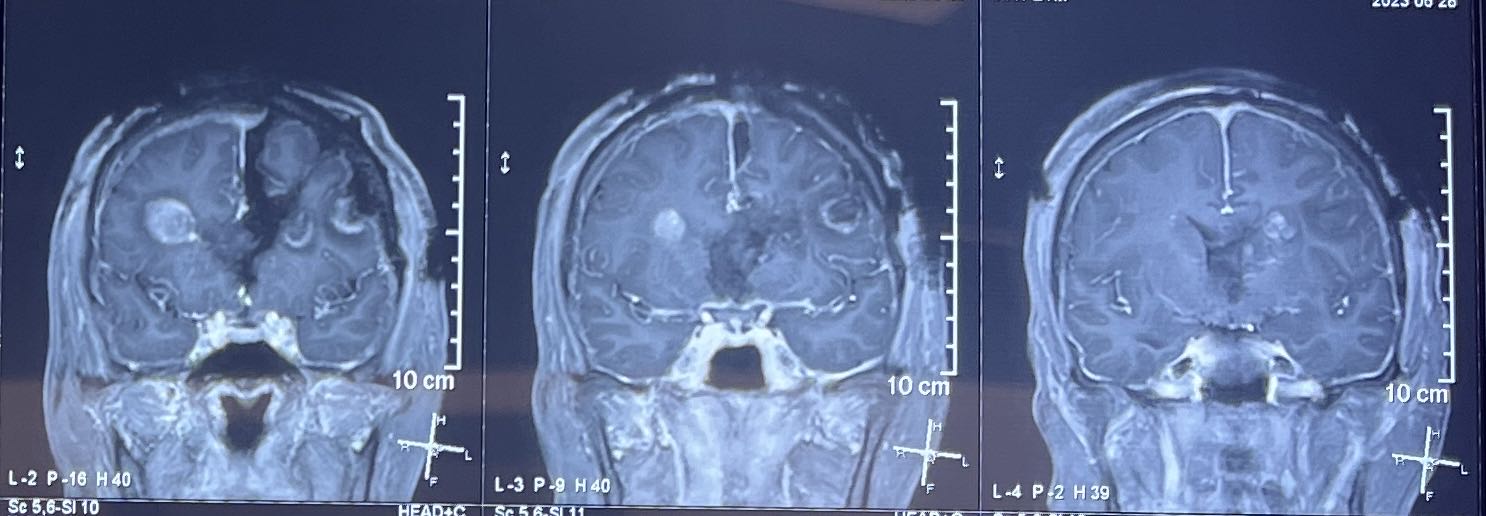

术前增强核磁:

片子可见肿瘤多中心, 累及范围广,包括胼胝体膝部,穹窿体,下丘脑,双侧额叶,左侧脑室前壁。